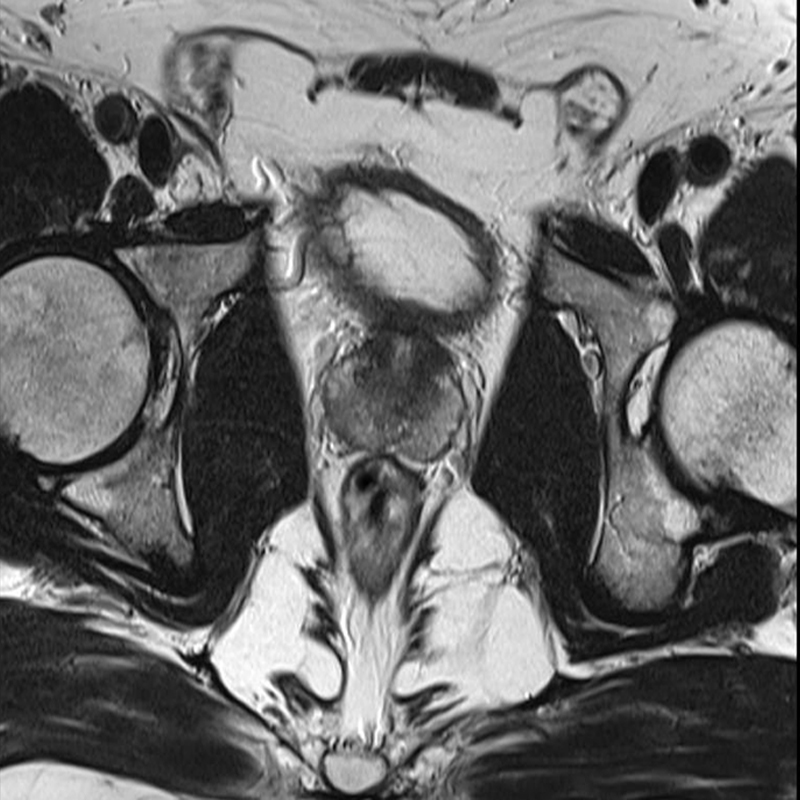

Beyin, omurilik, kas-iskelet sistemi ve yumuşak dokuların değerlendirilmesinde üstündür.

o Beyin, omurilik, kas-iskelet sistemi ve yumuşak dokuların değerlendirilmesinde üstündür.